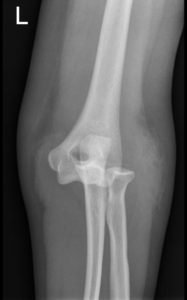

Posterior Elbow Dislocation, AP XRay, dislocated. JETem 2016

Posterior Elbow Dislocation